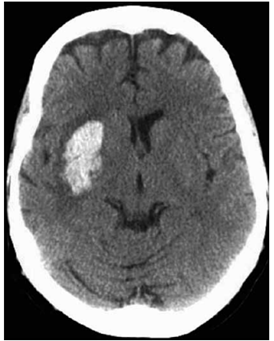

Mulher de 56 anos de idade com abuso crônico de álcool e hipertensão arterial é levada ao serviço de saúde com quadro de início agudo de hemiparesia esquerda e disartria. A tomografia de crânio realizada é mostrada a seguir.

Enunciado 4376912-1

Nessa situação, a etiologia subjacente que, mais provavelmente, é responsável pelo achado neurológico da paciente é